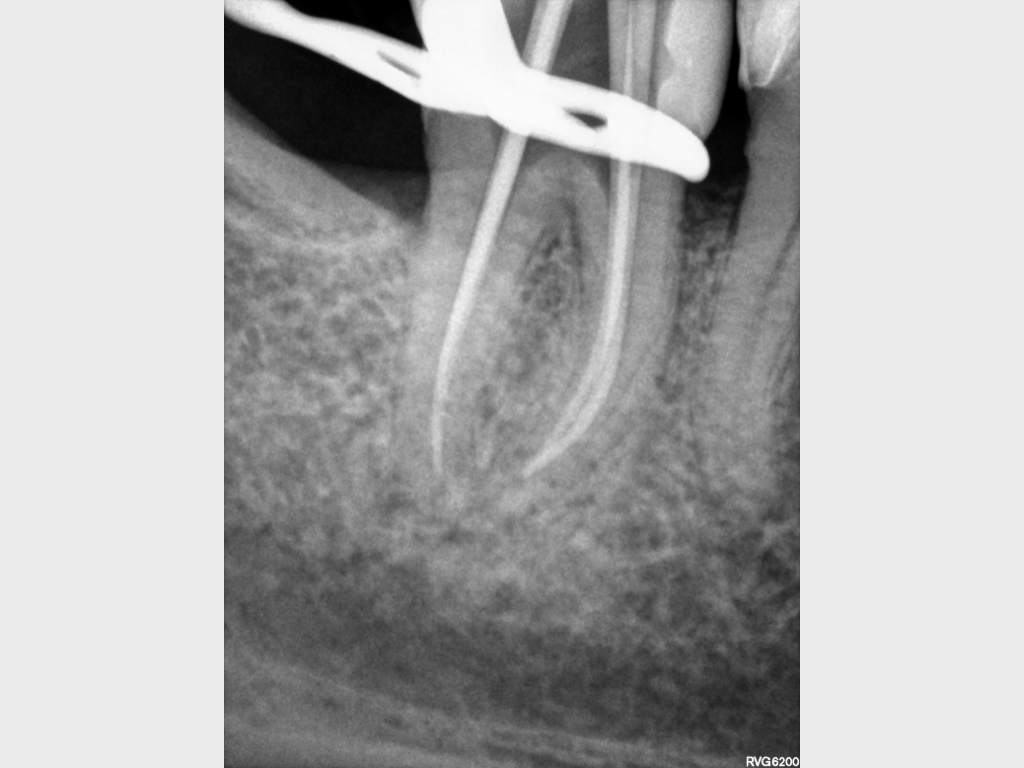

9703.005

24. November 2020

1024 × 768

Recall